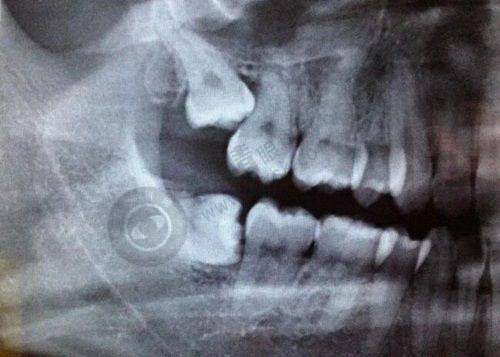

衢州贝加尔口腔是衢州美芽健康管理有限公司柯城贝加尔口腔诊所,属于本地民营口腔诊所。它可不是随便开的,是由衢州市柯城区卫生健康局严格审批建立的,备案编号为MADHGFBA633080215D2202。诊疗科目包括口腔科(含口腔种植,口腔颌面医学影像)。有了这样正规的资质,就好比给大家吃了一颗定心丸,从这方面来看,衢州贝加尔口腔诊所是可靠的。

精良的设备:衢州贝加尔口腔在种植牙方面引进了欧洲设备,这些精良的设备能够更精细地进行种植手术,提高手术的成功几率和成效。